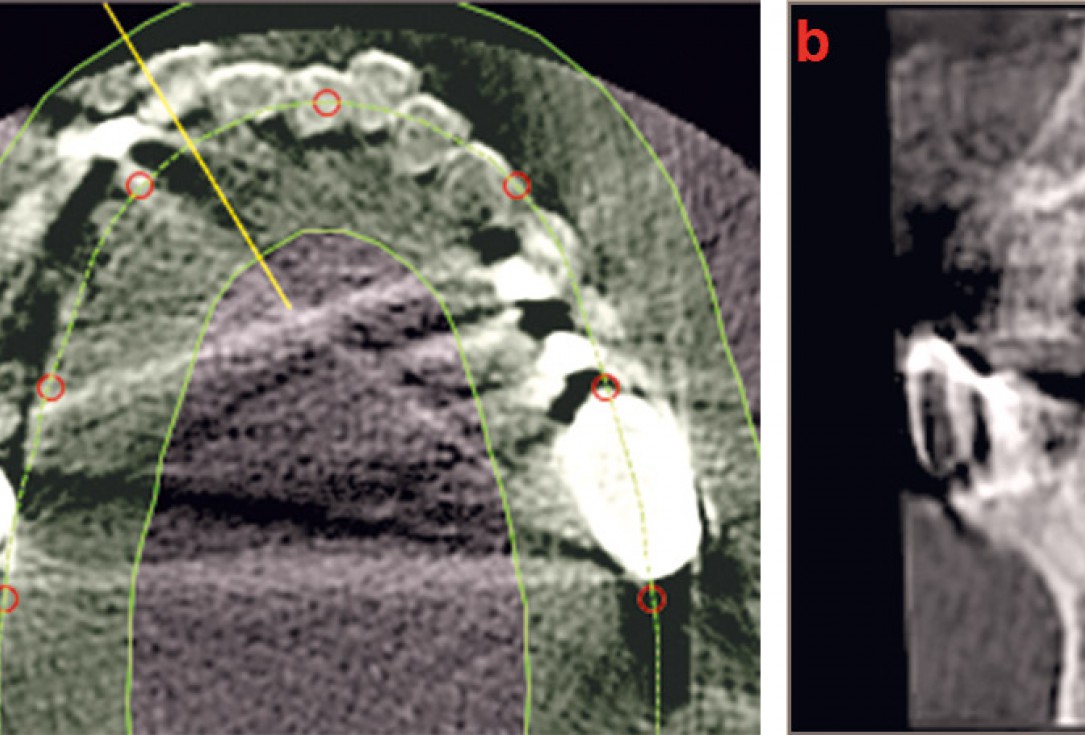

09 / 22 - Post-OP CBCT recording demonstrates the pronounced horizontal augmentation

Three-dimensional augmentation with maxgraft® cortico - M.Sc. E. Kapogianni